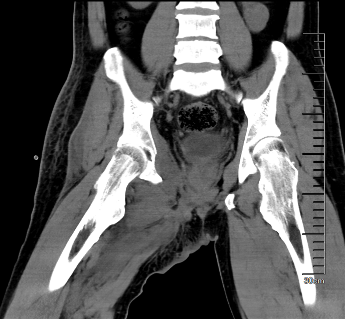

图片 4.png图片 5.png图片 6.png

术前MR